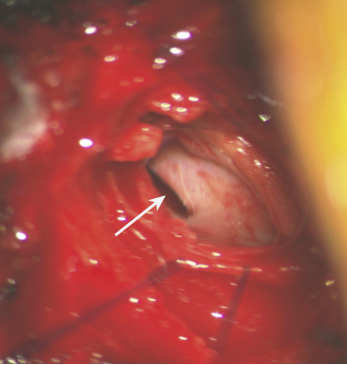

图2 硬脊膜缺损

CSFL是指手术操作引起硬脊膜破损,导致腰椎术后脑脊液通过手术切口流出体外。椎管或神经根管严重狭窄的患者,手术减压和分离极易损伤硬脊膜和蛛网膜,导致CSFL。虽然CSFL相比于SSI等并发症较为少见,但是,CSFL也是腰椎术后早期导致URP的常见原因。术后一旦发现应立即采取硬膜外注射血液、纤维蛋白胶和手术等方式治疗。如处理不当会引起低颅压性头痛、发热,影响手术切口愈合,甚至导致脑脊髓膜炎等严重后果。Durand等筛选了86 212例多种脊柱疾病患者,发现172例患者发生迟发型硬脊膜撕裂,其中170例需要再次手术治疗。Liu等提出在3 936例后路腰椎手术患者中有11例发生CSFL并接受手术,通过再次手术缝合硬脊膜并放置引流管1周后,11例患者情况基本好转。Deukmedjian等报道了255例腰椎间盘退行性疾病患者接受单节段或多节段腰椎减压融合治疗后,有1例再次手术修补CSFL。Hall等的研究中,150例患者行腰椎后外侧融合术后,2例发生CSFL并接受手术治疗。Bydon等对500例行1~3节段腰椎椎板切除术的患者分析,发现8例术后发生CSFL,1例需要再次手术,其余7例卧床休息后痊愈。CSFL常见于脊柱术后早期,症状较轻的患者可采取保守治疗,然而保守治疗无效或症状严重的患者应手术缝合硬脊膜。